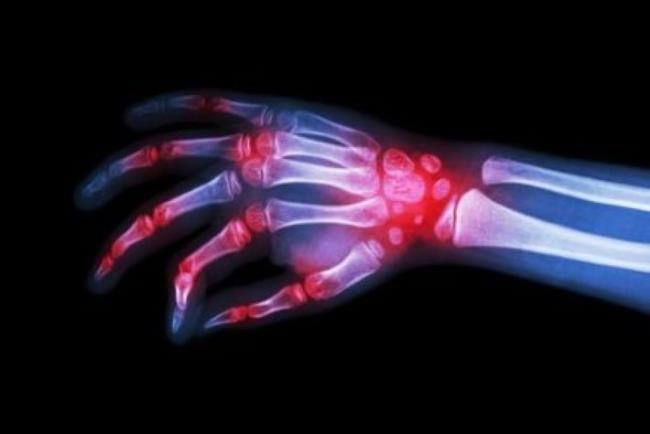

השימוש באתאנרספט הוא עבור מחלות דלקתיות שמערבות את המערכת החיסונית: דלקת פרקים שגרונית,דלקת חוליות מקשרות, דלקת פרקים פסוריאטית (שילוב של פסוריאזיס ודלקת פרקים) ופסוריאזיס.

הטיפול בדלקת פרקים שגרונית ינתן לרוב בשילוב עם מתוטרקסאט.

אתאנרספט מתאימה לטיפול גם בילדים ובמתבגרים,הסובלים מדלקת פרקים שגרונית (juvenile rheumatoid arthritis). ומפסוריאזיס, בתגובה לא מספקת או היעדר יכולת לקבל טיפול אחר. לא מדובר בריפוי המחלות הנ"ל אלא בהפחתת תסמיני הדלקת ובאופן זה עיכוב הנזק הנגרם לרקמות השונות.

צילום רנטגן